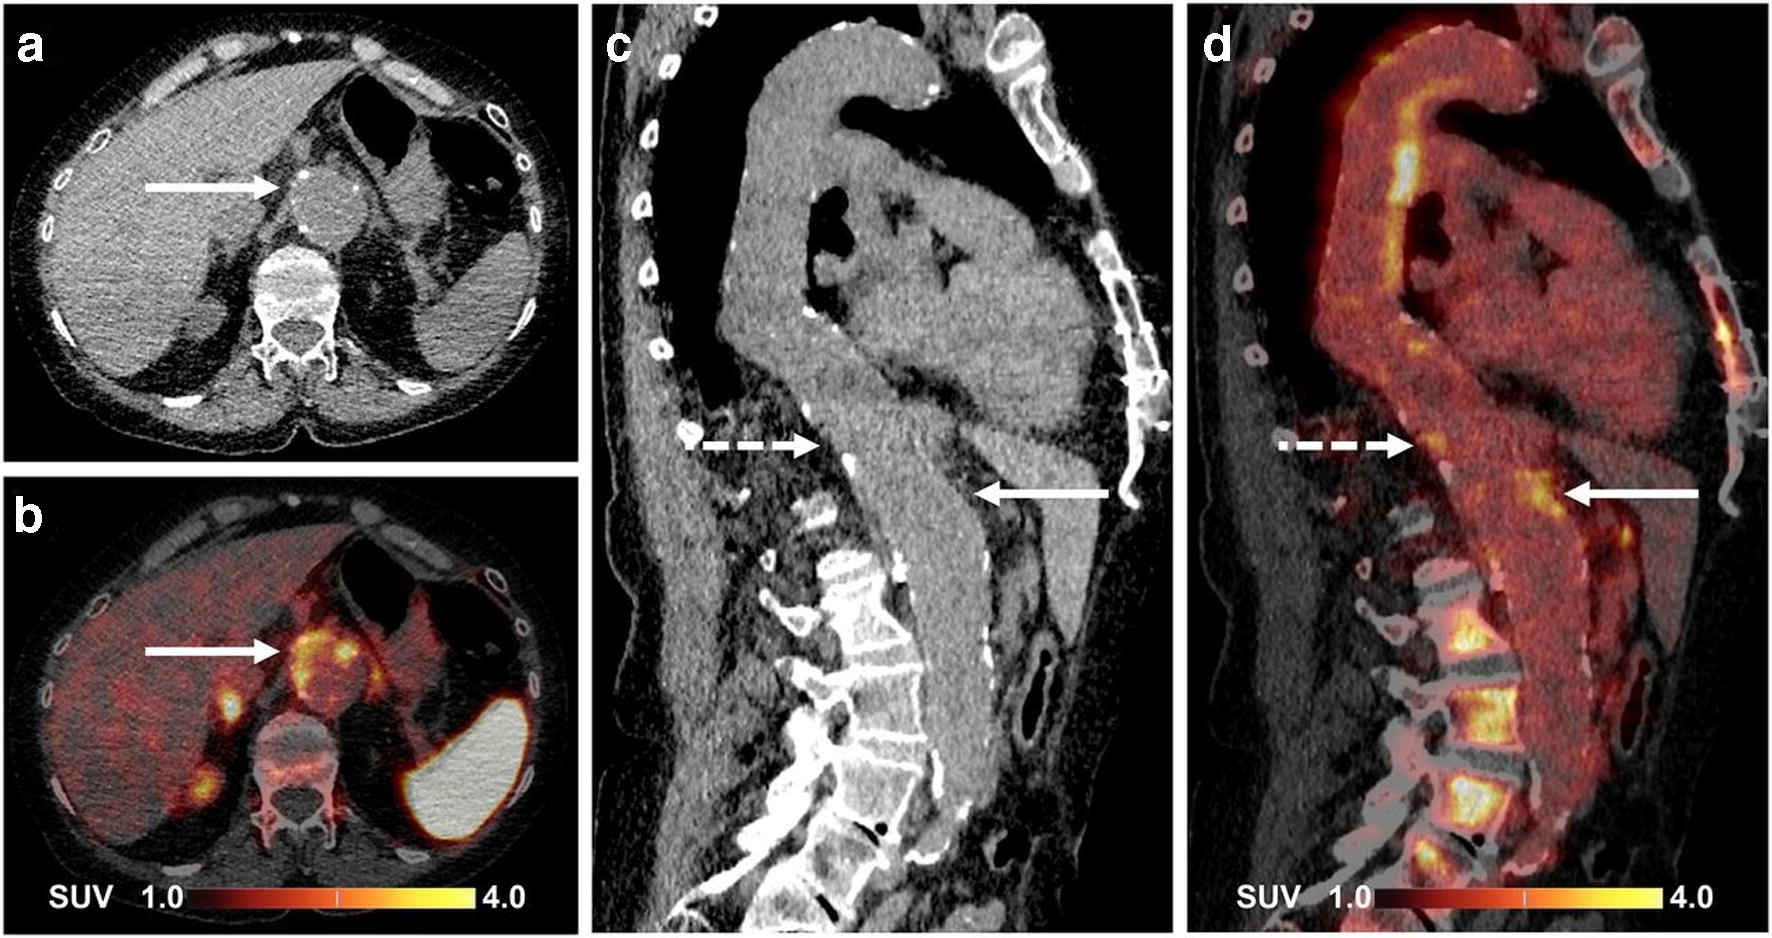

Figure 5 from Radionuclide imaging of the kidney in tuberous sclerosis